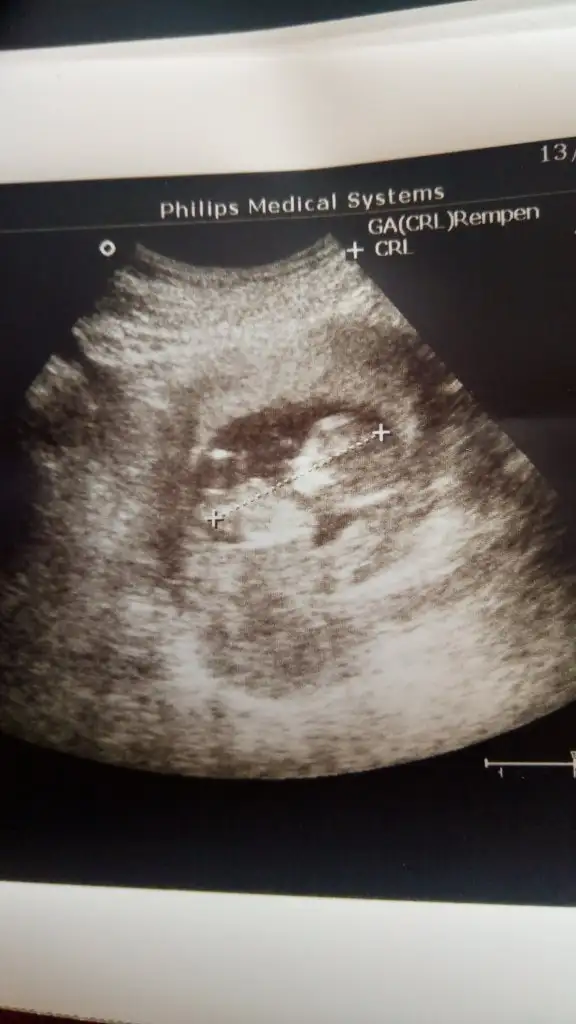

Merhaba banada yorum yapar mısınız. 11+4 de çekildi

Kız gibi sanki 13 hafta olursa paylaşın çok net değil USGIkra meyra canım yorumlar mısın

Kaç haftalık USG sanki erkek gibi emin olamadım 11 12 13 haftalar olmalı tekrar USG paylasin